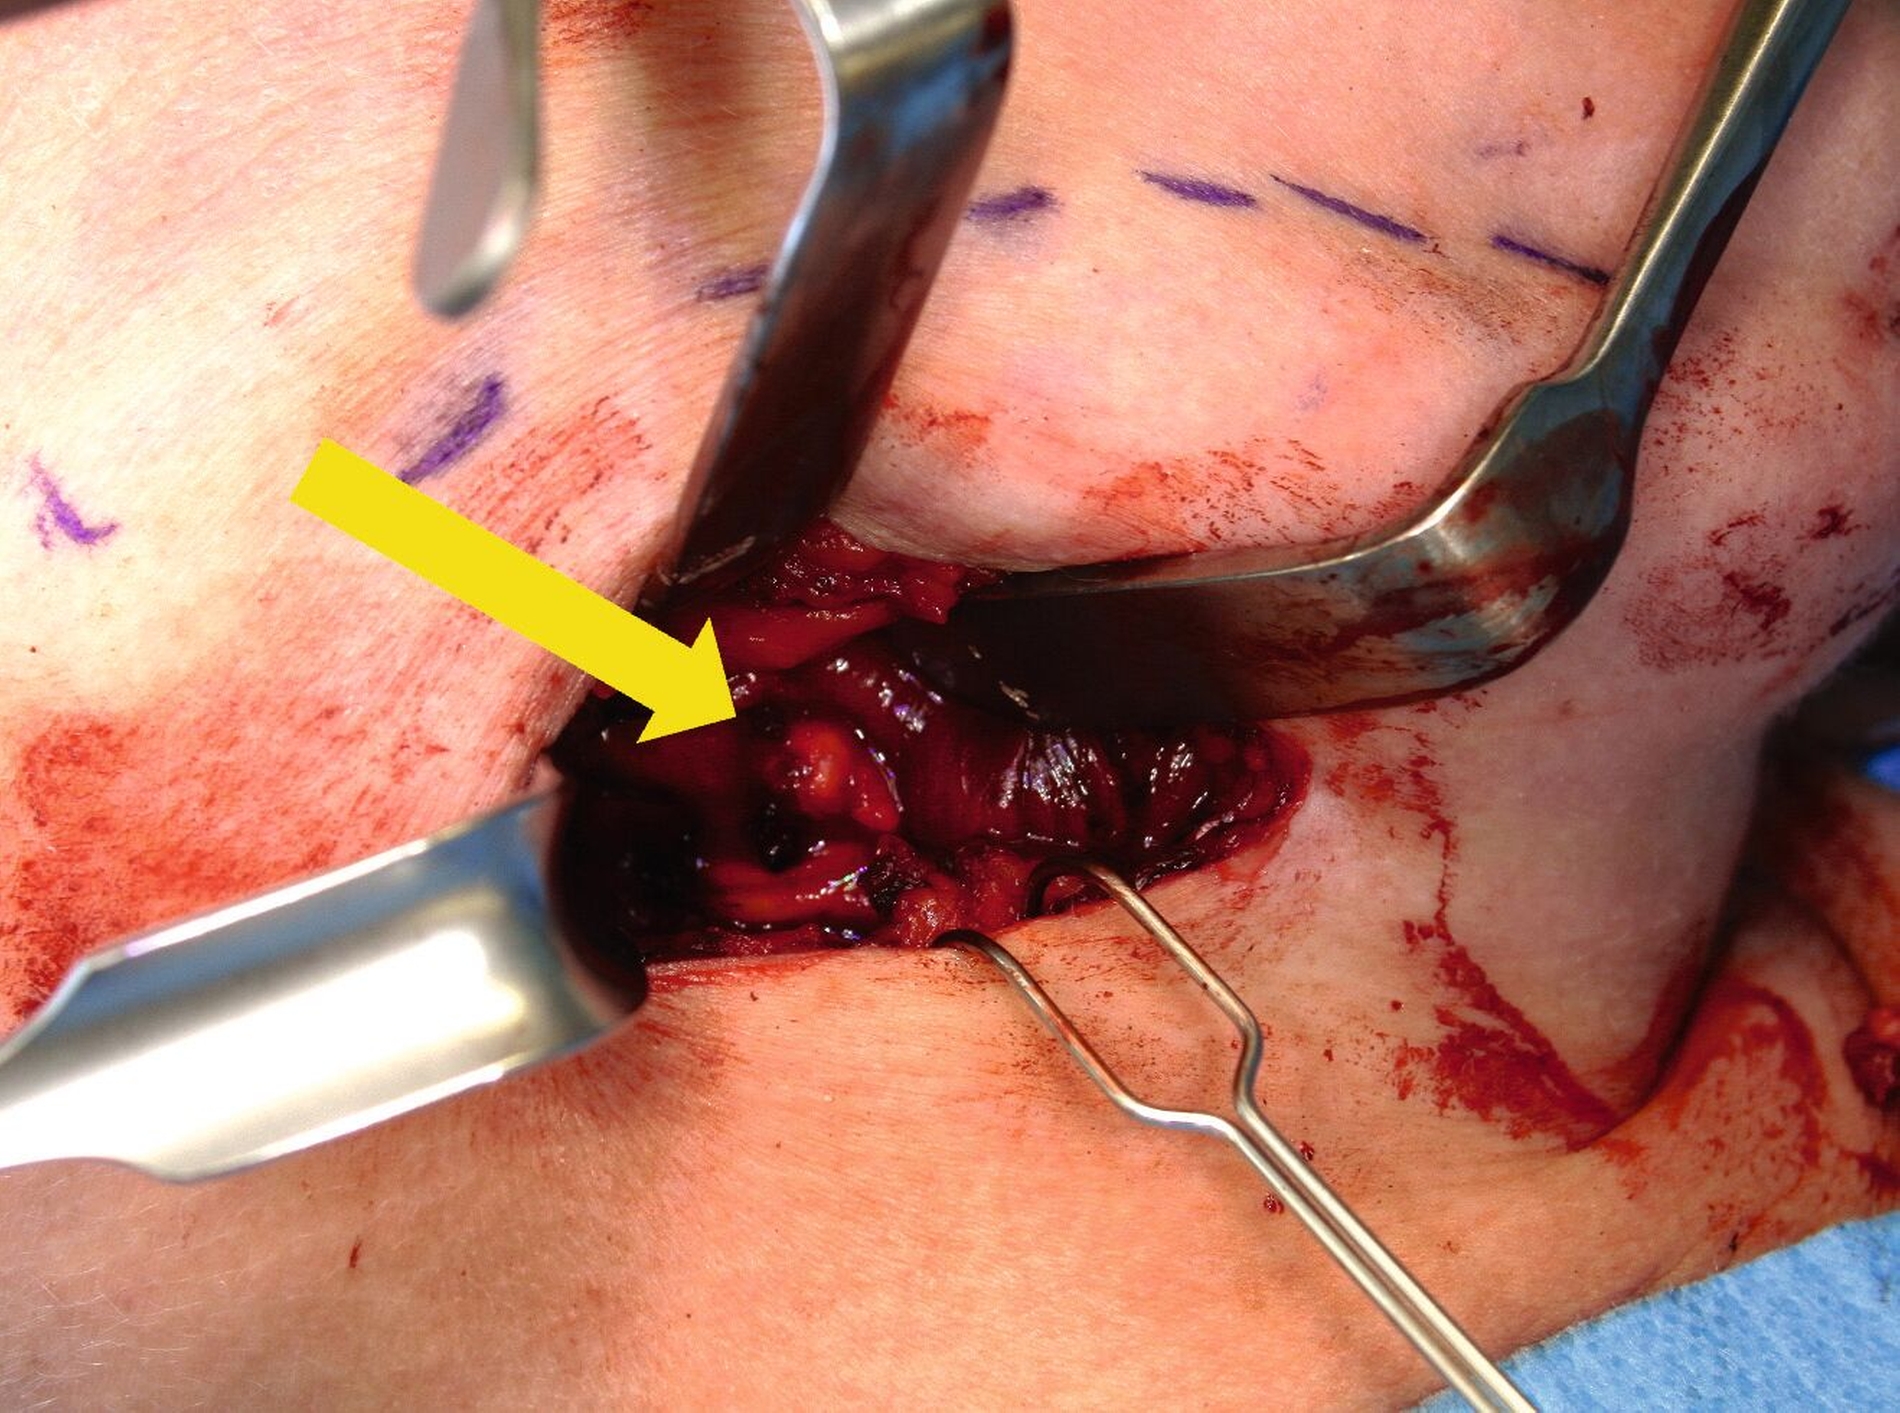

Nach eingehender Beratung aller potenziellen therapeutischen Optionen, insbesondere einer erneuten Sialendoskopie, mit der Patientin, wurde entschieden, die betroffene Drüse inklusive des Steins in Intubationsnarkose zu entfernen. Der Eingriff erfolgte komplikationslos während eines zweitägigen stationären Aufenthalts. Die Submandibulektomie wurde über einen extraoralen Zugang von etwa 4 cm durchgeführt, wobei die angrenzenden Nerven geschont wurden; und der Stein wurde erfolgreich entfernt (Abbildungen 4 und 5). Um keine weiteren Steine zu übersehen, wurde intraoperativ der Wharton-Gang sondiert und exstirpiert (Gang-Stripping). Die Patientin berichtete während der Nachsorgephase über keine Beschwerden mehr – und die Narbe war aufgrund ihrer Lage in einer Halsfalte kaum sichtbar.